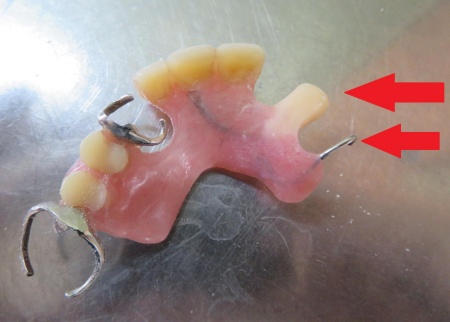

拝見したところ、左上の歯が折れて歯根だけが残っている状態でした。

これが原因で、入れ歯を固定する金属のバネ「クラスプ」をかける歯の土台が失われ、入れ歯が安定しなくなっています。

①増歯:入れ歯にプラスチック製の人工歯を加え、折れた歯を補う処置

②新たなクラスプの製作:入れ歯の安定を図るため、左上の前歯から4番目の歯にかけるバネを追加する

折れた部分に合う人工歯を慎重に選び、入れ歯に丁寧に取り付けました。

続いて、左上の前から4番目の歯に合わせて金属ワイヤーを成形し、新しいクラスプを作製します。